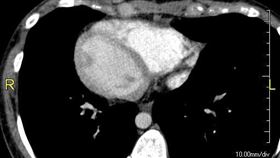

獨/「鏡面人」心臟在右邊 醫:10年一遇

您聽過「鏡面人」嗎?他們外觀與一般人無異,內臟位置卻...